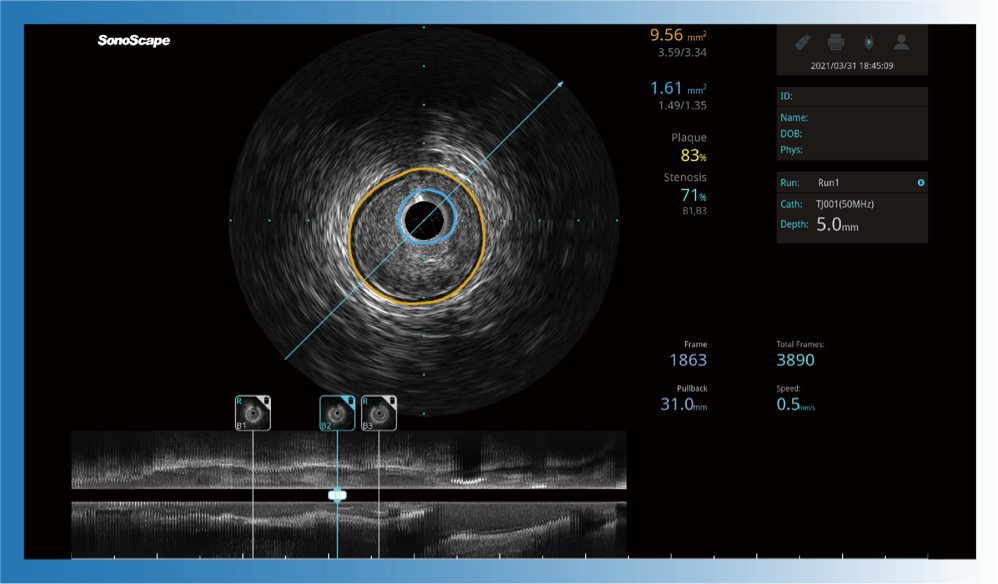

新葡的京集团8814检测站宽频IVUS图像

对比传统IVUS导管成像,新葡的京集团8814检测站宽频IVUS图像的近场支架梁显影更细腻,远场中膜外血管仍清晰可辨,兼顾远中近,兼顾分辨力与穿透深度

一键智能描迹,自动测量斑块负荷、面积狭窄率等指标,准确率高于90%